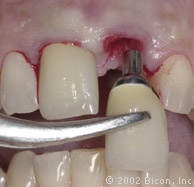

Установка двух 3.0mm Impression Post

Снятие слепка и подбор цвета